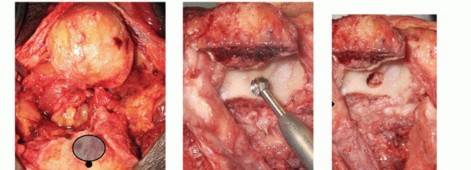

With the ulnar nerve gently medially retracted, use a periosteal elevator to define the plane between the medial triceps and the posterior humerus, proximally to the triceps attachment at the olecranon. Carry the dissection across the posterior humerus to the lateral aspect of the triceps, exiting posteriorly to the lateral intermuscular septum. Use the elevator to lift the triceps, with blunt dissection, by sliding the shaft of the elevator proximal and distal in the interface (TECH FIG 2A).

Develop the lateral triceps-lateral intermuscular septum margin to the lateral attachment of the triceps on the olecranon. Release the common extensors and lateral collateral ligament complex from the lateral fracture fragment. Resect the lateral fracture fragments, having firstly cleared them of soft tissue attachments (TECH FIG 2B).

While in the lateral corridor, visualize the radial head and resect sufficient head to prevent abutment on the prosthesis.

- TECH FIG 2 • A. A periosteal elevator is introduced between the triceps and the humeral shaft, and the two structures are separated by sliding the elevator proximally and then distally to the level of the triceps insertion. B. The lateral corridor is defined, and lateral fragments are removed.